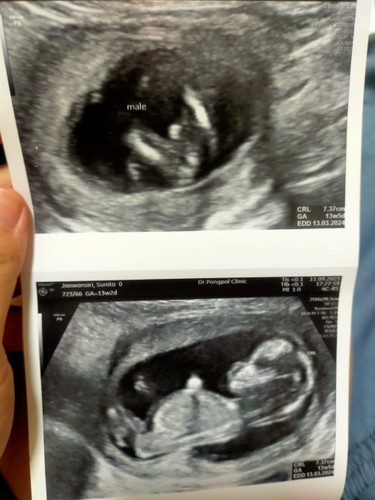

13w2d.โชว์เพศแล้วค้าบบ

คุณหมอบอกว่าผมมีจู๋ครับ อ้าขาโชว์คุณหมอกับแม่ไม่ให้แม่ลุ้นเลยครับ🤣🤣 #ทีมมีนาคม67 #ท้องสอง